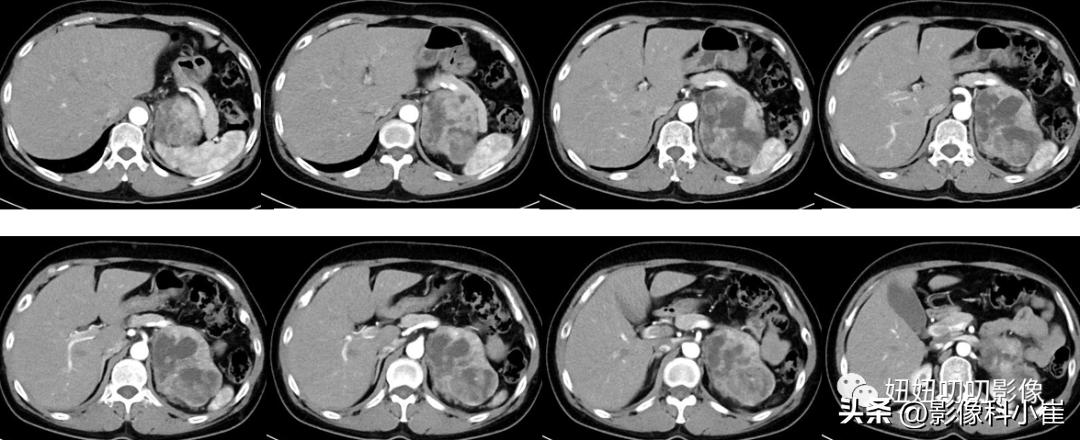

病史:

女,57岁,主诉:查体发现左肾上腺占位10天。最近测血压最高150/85mmHg。

影像描述:

左侧肾上腺区见一团块状等长T1 等长T2 混杂信号,边界尚清,DWI示部分弥散受限,T1 反相位信号未见明显减低,最大截面约9.7X7.0X71,其内见点状短T2 信号,增强扫描呈明显渐进性不均匀强化,邻近组织受压。右侧肾上腺形态、信号未见异常,增强后未见异常强化。双肾见小圆形长T1长T2 信号,边界尚清,增强扫描未见明显异常强化。腹腔及腹膜后未见明显增大淋巴结。腹腔内未见明显液体信号灶。